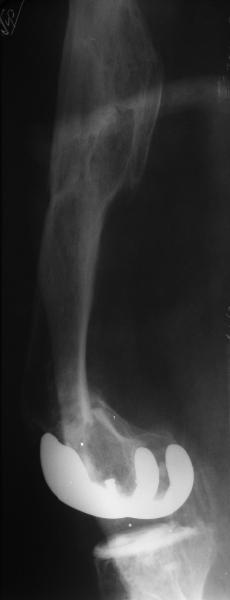

Добрый день! В нашу больничку поступил пациент после бытовой травмы - упал, подвернув ногу. На RG-граммах перелом дистального метаэпифиза бедренной кости. Пациент спутанно рассказывает, где и как он лечился раньше.10 лет назад - коррегирующая остеотомия по поводу деформирующего артроза коленного сустава, 3 года назад в 1 градской больнице г. Москвы выполнено эндопротезирование коленного сустава,площадка большеберцовой кости, со слов пациента, деформировалась около года назад (на фоне остеопороза). Сейчас получил травму в результате падения с высоты собственного роста.Что посоветуете?

на снимке признаки loosening и тибиального и феморального компонентов я думаю нужна ревизия если нет возможностей то артродез и конечно исключить инфекцию . успехов .

Мне представляется следующее: Если дистальный отдел бедра расколот и в сагиттальной и во фронтальной плоскостях, как видно на рентгенограммах, и при этом есть смещение отломков относительно друг друга и бедренного компонента эндоаротеза, разве от может оставаться стабильным? В случае отсутствия проблем с тибиальным компонентом, можно было бы надеяться только на остеосинтез и стабилизацию, но если предполагается ревизия в ближайшие месяцы/год, то не лучше ли за один раз решить несколько проблем?